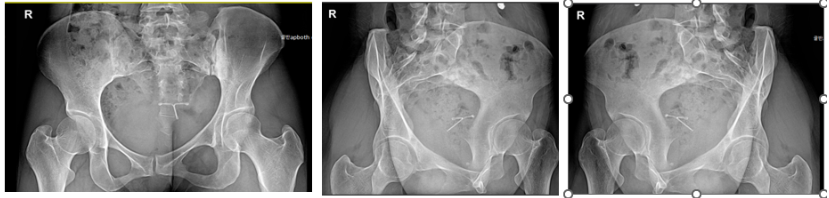

신경학적 검사상에 좌측 천장관절염을 의심하게하는 압통을 비롯한 소견을 보였고, 방사선소견상에는 골반이 많이 틀어져있으며 좌측 천장관절에 방사선 불투과성(radiopaque) 변화 소견이 있었습니다. 환자분은 3시간정도 차를 타고 가야하는 거리에서 오셨고, 10년 가까이 만성통증에 시달리는 분이라 정확한 진단이 필요하여 MRI 검사를 시행하였습니다.

골반MRI 검사상에는 좌측 천장관절염이 진단되었습니다.